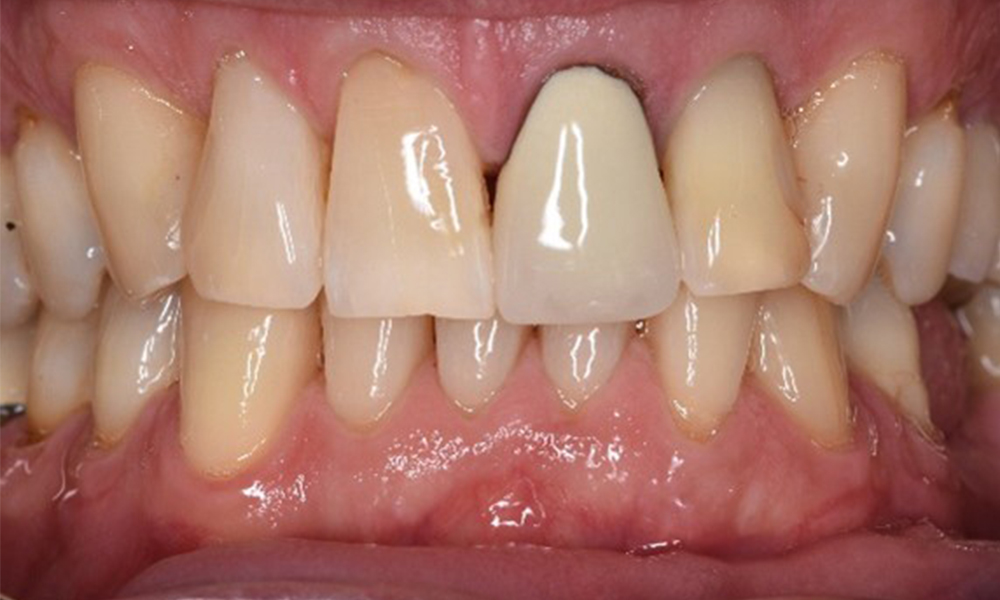

In terms of instruments, specific procedures are required for use with implants. In order to preserve the surface of the implant while cleaning it effectively, it is essential to choose suitable powders and instruments, such as the targeted use of air polishing devices with special periodontal tips. Which powder is most suitable can be determined according to the needs and risk. For example, in addition to the appropriate degree of abrasion, dietary requirements (including sugar-free, low-salt) may also be taken into account.

On the basis of the stable periodontal and peri-implant situation, it is recommended that the patient should have check-ups every six months.